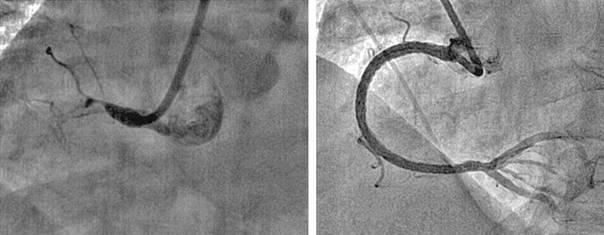

Коронарная ангиография является одной из процедур в кардиохирургии. Этот метод позволяет визуализировать такие изменения коронарных сосудов, как закупорку, сужение, повторное сужение, тромбоз или аневризматическое расширение просвета этих сосудов. Закупорка просвета артерий приводит к возникновению инфаркта миокарда, который может быть остановлен (в условиях специально оборудованного стационара) благодаря применению тромболитической терапии (рис.2) и/или установки стента (рис.3). Сейчас простая процедура коронарной катетеризации занимает не более 5-8 минут, при частоте осложнений 0,1%. Стентирование - весьма эффективный метод, во время выполнения ангиопластики при надувании баллончика на нем находится стент – цилиндрической формы каркасная проволока, которая расширяет стенозированный участок сосуда и не позволяет просвету артерии сужаться в дальнейшем. (Рис.2.) На стент может быть нанесено лекарственное вещество, способствующее эпителизации и предотвращающее тромбообразование.

Рис.3 Рис.3

Ангиографическое изображение до (слева) и после (справа) полную окклюзию правой коронарной артерии. Окклюзия характеризуется сужением, нехваткой коллатералей и отсутствием кальцификации. Было установлено 3 стента с лекарством (3.5 x 33, 3.5 x 33, and 3.5 x 23).